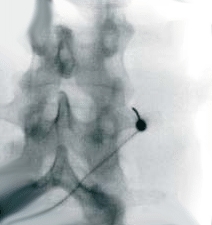

Thermokoagulation

Thermokoagulation ist Schmerzbehandlung durch Erhitzung. Hierbei werden mit einer Hitzesonde unter örtlicher Betäubung einzelne Nervenfasern verödet.